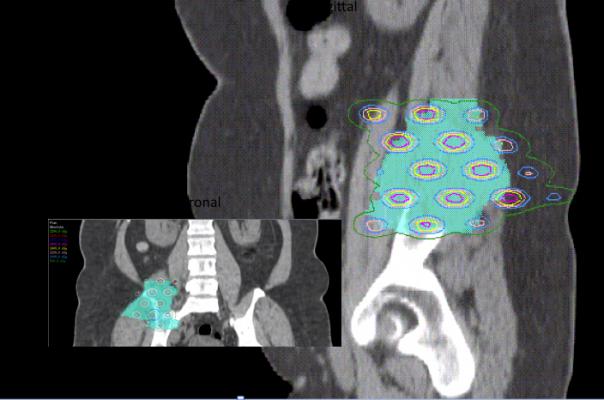

“Heavy ion radiation, on the other hand, delivers therapy that is both more potent and more precise than conventional as well as proton therapy,” Choy said. “It offers treatment to normally radioresistant tumors as well as improved dose conformation with even better sparing of normal tissue structures close to the target. This is important when treating areas that are close to sensitive structures such as the spine and brain, where we want to minimize exposure as much as possible while achieving maximal impact to the tumor.”